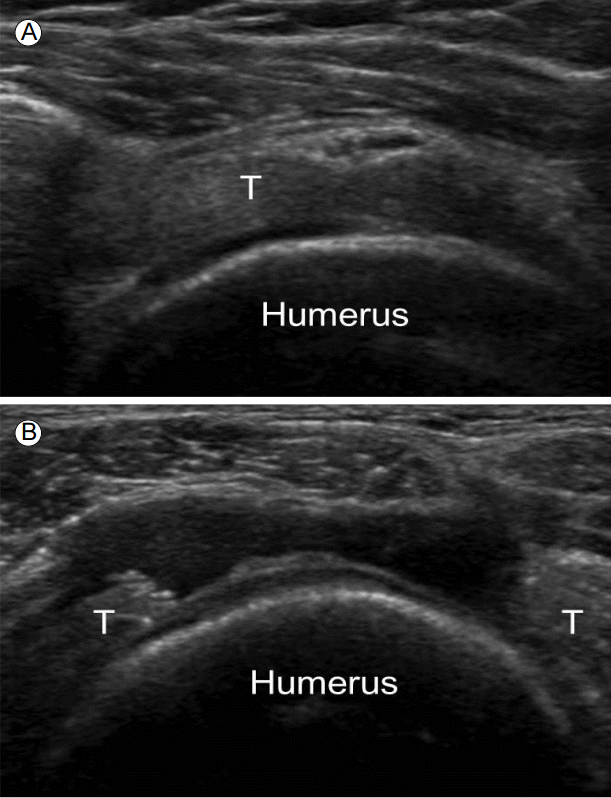

회전근개 파열

파열된 두께에 따라 부분층(partial-thickness) 파열과 전층(full-thichness) 파열로 나뉘고, 부분 파열은 파열된 부위에 따라 힘줄내(intrasubstance), 윤활낭면(bursal surface)과 연골면(articular surface) 파열로 나뉘며, 힘줄이 큰거친면(greater tuberosity)에 부착하는 부위에서 잘 발생한다. 초음파 소견으로는 고에코성의 균질한 실타래 에코가 갑자기 중단되어 국소적인 저에코성 또는 무에코성 병변이 존재하는 것이 탐촉자의 두 직각 면에서 모두 관찰되고 탐촉자에 의해 힘줄 사이가 압박이 될 수도 있다(Fig. 5) [5]. 그러나 출혈에 의해 파열 부위가 오히려 고에코성으로 관찰되거나, 뚜렷한 결함 없이 힘줄이 점진적으로 얇아지거나, 오래된 광범위 파열인 경우 힘줄이 끌어당겨져 관찰되지 않을 수도 있다.